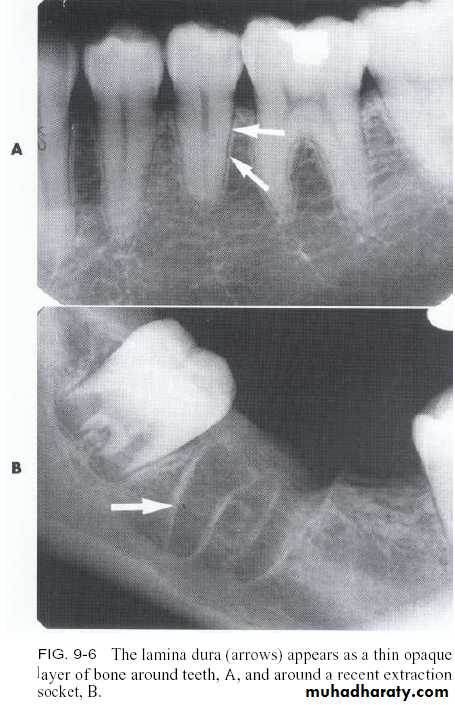

Alveolar crestLamina dura

Radiograph of mandibular premolar area. Radiograph shows the (1) submandibular fossa, (2) a thin radiolucent line indicating the periodontal ligament space, (3) thin radiopaque line representing the lamina dura, and (4) the mental foramen